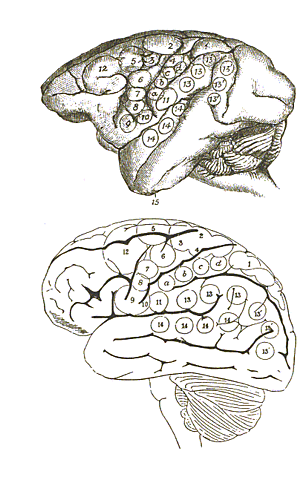

Frenología

Franz Joseph Gall reúne a individuos con talentos únicos y túmulos peculiares en el cráneo. Considerado como el creador de la frenología. Halló 26 áreas en el cerebro y creía que eran órganos separados, por ejemplo; el órgano del amor, el órgano de la espiritualidad, etc.

• Franz Joseph Gall

Franz Joseph Gall

Por medio de una carta se le pide a Gall dejar su país (Alemania) por sus ideas sin sentido. Franz se trasladó a Paris y ahí publica sus mejores obras sobre la organología / frenología.

Gall hace una publicación sobre frenología. Es decir, todos los procesos mentales se dan en el cerebro y tienen un área específica para cada uno.